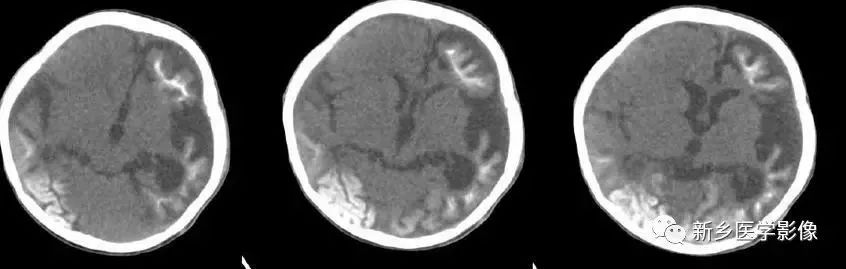

❶ 交通性脑积水

又称脑室外梗阻性脑积水,是由四脑室出口以后脑脊液循环通路障碍所致的脑积水。常位于蛛网膜下腔,以基底池最常见。

主要原因包括脑膜炎、蛛网膜下腔出血、脑膜转移、外伤、静脉窦血栓、颅脑手术后和脑脊液吸收功能障碍等。临床表现主要由颅压增高所引起.,可表现有头痛、呕吐、复视和视乳头水肿等。

交通性脑积水时,第四脑室扩大通常出现较晚,故早期时,可仅表现有侧脑室和三脑室扩大。主要应与导水管狭窄之梗阻性脑积水区别。MR矢状位T1加权图是直接观察导水管有无狭窄的最好方法。

另外需要与普遍性脑萎缩区别:脑萎缩时沟脑裂增宽,而脑积水时脑沟变窄消失或正常;脑萎缩时三脑室扩大较明显,脑积水时三脑室扩大不明显。到晚期,交通性脑积水出现整个脑室系统普遍扩大,而脑沟正常或变窄消失。